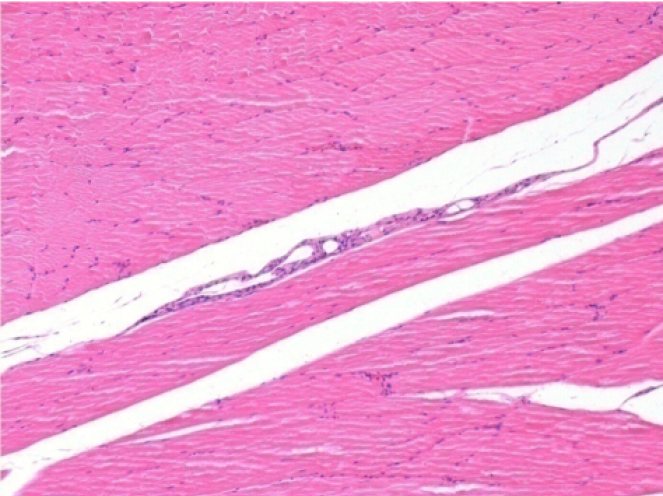

3 mesi dopo Iniezione di Endopeel

Scatola Nr 4

3 mesi (Giorno90) dopo iniezione 0.1ml di Endopeel nel muscolo pretibiale destro ( Dx)

Sx : Controllo-100x-Giorno90

Dx:100x-Giorno90